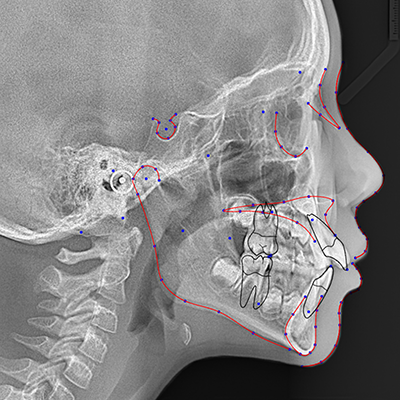

رادیولوژی سفالومتری یکی از روشهای تخصصی در حوزه رادیولوژی دهان، فک و صورت است که برای بررسی دقیق ساختار استخوانی و بافت نرم ناحیه سر و صورت استفاده میشود. این نوع تصویربرداری بیشتر در ارتودنسی و جراحیهای فک کاربرد دارد، زیرا امکان ارزیابی دقیق روابط فکی، زاویهها و تناسب اجزای صورت را فراهم میکند. در سفالومتری با دستگاههای دیجیتال پیشرفته و کمترین میزان اشعه انجام میشود تا بیمار در شرایط ایمن و با کیفیت بالای تصویر تحت بررسی قرار گیرد.

در این روش، تصویر جانبی یا قدامی-خلفی از سر بیمار تهیه میشود که شامل جزئیات کامل استخوانهای فک، دندانها و حتی برخی بافتهای نرم صورت است. متخصصان ارتودنسی از نتایج رادیولوژی دهان، فک و صورت به روش سفالومتری برای طراحی طرح درمان، پیشبینی نتایج ارتودنسی و بررسی تغییرات پس از درمان استفاده میکنند. کیفیت بالای تصاویر در رادیولوژی دکتر بصیری به پزشکان کمک میکند تا با دقت بیشتری تصمیمگیری کنند.

یکی از مزایای مهم سفالومتری دیجیتال این است که تصاویر تهیهشده بهصورت فوری و با وضوح بالا قابل مشاهده و تحلیل هستند. این امر باعث میشود که فرایند تشخیص و برنامهریزی درمان سریعتر انجام گیرد.به طور کلی،این رادیولوژی ابزاری ارزشمند در تشخیص و درمان مشکلات فکی، ناهنجاریهای اسکلتی صورت و طرحریزی درمانهای ارتودنسی است.

تصویربرداری از نیمرخ:

سفالومتری معمولاً به صورت جانبی (از نیمرخ) انجام میشود، به این معنی که تصویر از کنار سر گرفته میشود.

هان و فمتصویر دقیق از ساختارها:

این روش تصویربرداری، جزئیات دقیقی از استخوانها، دندانها و بافتهای نرم را نشان میدهد.

آنالیز و اندازهگیری:

تصاویر سفالومتری قابلیت اندازهگیری و تجزیه و تحلیل دقیق زوایا و فواصل بین ساختارهای مختلف را دارند.